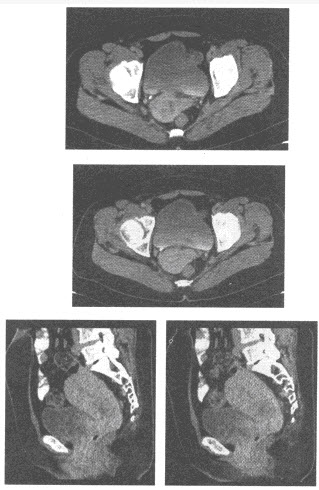

患者,男性,79岁,上腹部疼痛,不易缓解,吐咖啡色血液。行上腹部CT增强扫描,如下图